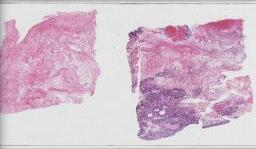

临床资料: 男,66岁,主诉:水肿、颈部淋巴结肿大,同期发现房颤。现病史:2020-05出现心悸伴颜面部、颈部、四肢水肿,尿量减少(约500ml/d),咳嗽、喘憋、活动耐量明显下降。外院完善ECG:“房颤”,颈部超声:双侧颈部淋巴结肿大。2020-06我院查:血常规:(-),肝肾功:LD365U/L,余(-);心肌酶(-);NT-proBNP1465pg/ml;感染:HBcAb(+),HBsAb(+);ECHO:LVEF69%,左房增大,心包少量积液。PET-CT示:1.左侧颈部(IV区、V区)、左侧锁骨上下、右肺门及后纵隔、腹膜后、肠系膜上多发代谢增高淋巴结(大小约0.5-1.6cm,SUVamx13.2),右心房、右心室及双侧心耳见多发代谢增高结节和肿物(大小约2.0×2.3-5.8×7.6cm,SUVamx24.6)、第2/3组小肠壁明显增厚且代谢增高异常(SUVamx17.1)。取左颈根部淋巴结送检。

大体所见: 淋巴结样组织数枚,直径0.5-2cm。